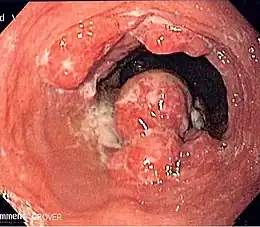

Description de cette image, également commentée ci-après

Endoscopie retrouvant un cancer de l'œsophage.